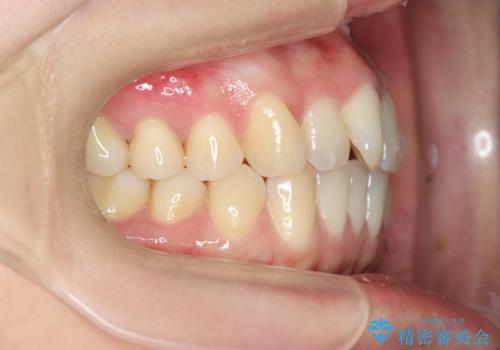

前歯のねじれを改善 マウスピース矯正インビザライン

- 目立つ前歯のねじれを改善したい、と矯正治療を希望され来院されました。

マウスピース矯正インビザラインを用いて綿密に治療計画を練り、美しい歯並びを手に入れるべく治療計画を立案します。